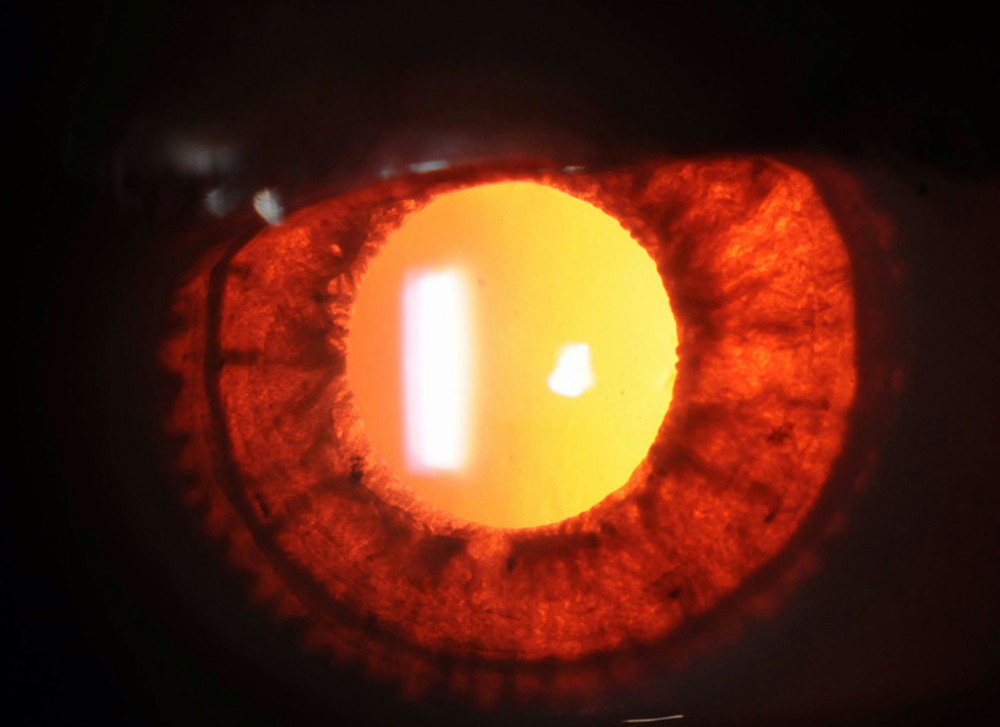

Staging schemes in albinism. Iris transillumination. Anterior segment

Staging schemes in albinism. Iris transillumination. Anterior segment Iris Transillumination Meaning Stanley thompson, md and randall e. Verdick, fops, at the university. An acute onset of severe photophobia and red eyes after a flulike illness or upper respiratory tract infection is the typical presentation. Iris tids are reported to be present in 91% [kruijt et. Iris transillumination defect (tid) is the loss of iris pigment epithelium. Bilateral severe iris transillumination, an. Iris Transillumination Meaning.